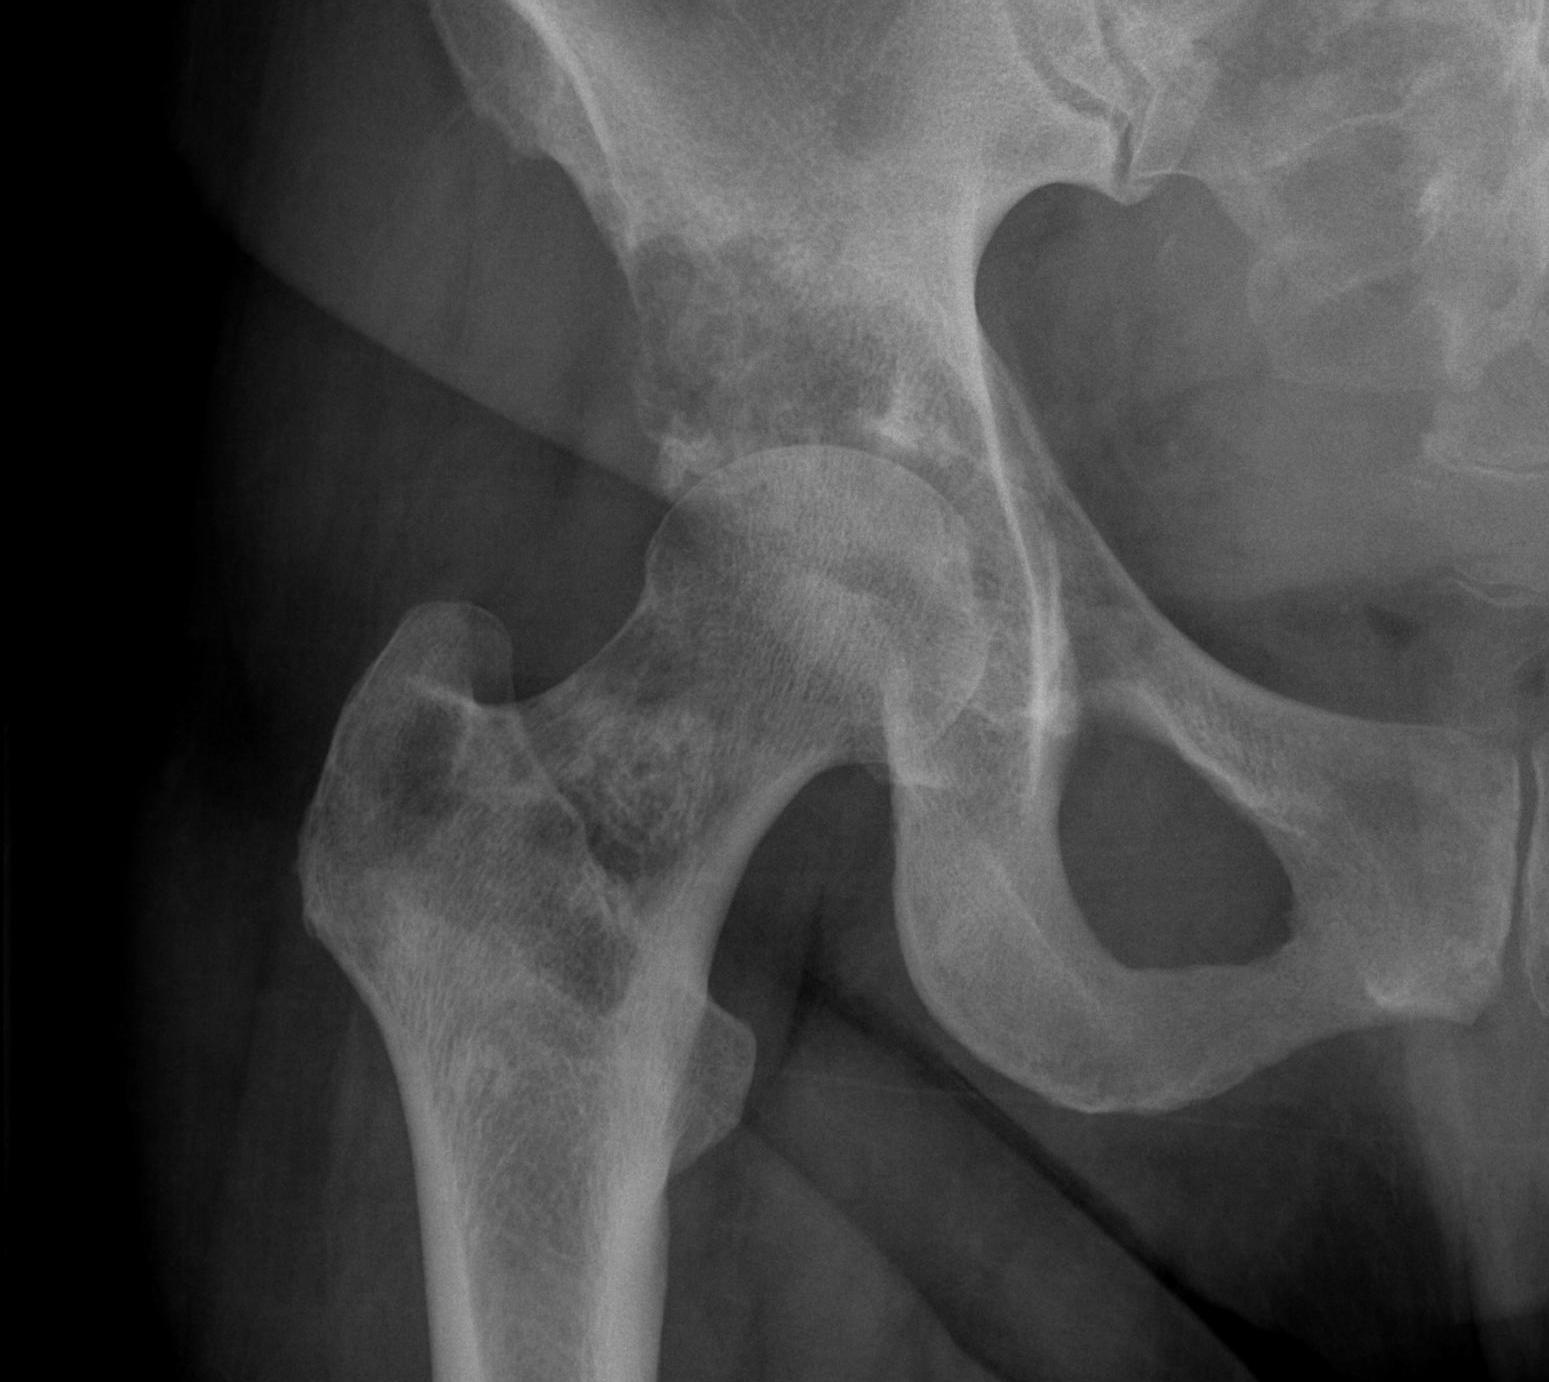

Femoral Neck pathological fracture / Major bone loss

Issues

- fracture unlikely to heal

- hemi versus THA

- long versus short stems

Hemi v THA

Consider life expectancy of patient

Femoral stem length

- 203 patients with proximal femoral metastasis treated with arthroplasty

- no increased revision rate with short stems

- increased complications with long stems, especially cardiopulmonary complications

Femoral neck stabilization

- sufficient bone for fixation?

- determine if lesions further down femur (xray entire femur)

- consider augmentation with PMMA / cement